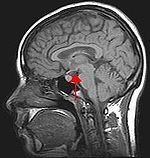

Biological psychology is the scientific study of the biological bases of behavior and mental states. Because all behaviour is controlled by the central nervous system, it is sensible to study how the brain functions in order to understand behaviour. This is the approach taken in behavioural neuroscience, cognitive neuroscience, and neuropsychology. Neuropsychology is the branch of psychology that aims to understand how the structure and function of the 'brain' relate to specific behavioural and psychological processes. Often neuropsychologists are employed as scientists to advance scientific or medical knowledge. Neuropsychology is particularly concerned with the understanding of brain injury in an attempt to work out normal psychological function.

The approach of cognitive neuroscience to studying the link between brain and behaviour is to use neuroimaging tools, such as to observe which areas of the brain are active during a particular task.

Neuropsychology involves the study of both healthy individuals and patients, typically who have suffered either brain injury or mental illness.

Cognitive neuropsychology and cognitive neuropsychiatry study neurological or mental impairment in an attempt to infer theories of normal mind and brain function. This typically involves looking for differences in patterns of remaining ability (known as 'functional disassociation's') which can give clues as to whether abilities are comprised of smaller functions, or are controlled by a single cognitive mechanism.

In addition, experimental techniques are often used which also apply to studying the neuropsychology of healthy individuals. These include behavioural experiments, brain-scanning or functional neuroimaging - used to examine the activity of the brain during task performance, and techniques such as transcranial magnetic stimulation, which can safely alter the function of small brain areas to investigate their importance in mental operations.